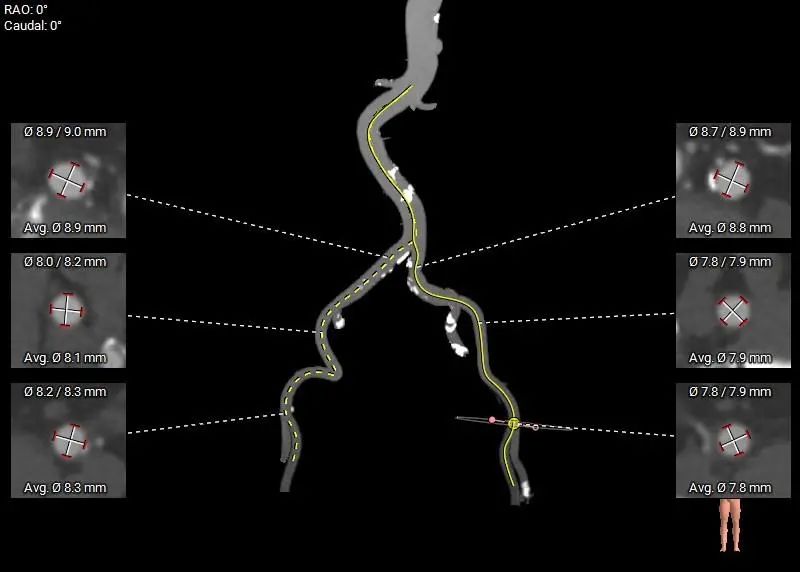

外周血管及主动脉弓解剖: